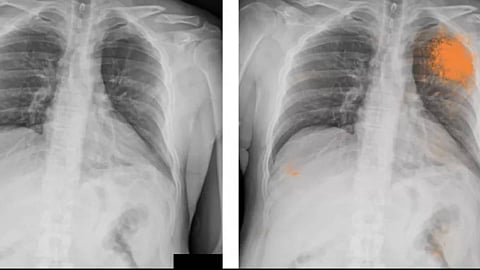

وكشفت أن الالتزام بحمية البحر المتوسط مرتبط بمخاطر منخفضة للإصابة بسرطان الرئة.

وأجرت الدراسة، المنشور نتائجها في «Frontiers in Nutrition»، تحليلًا تلويًا، وهو تحليل إحصائي يقارن نتائج الدراسات الحالية، لتسع مقالات سابقة قارنت التزام المشاركين بالنظام الغذائي بخطر الإصابة بالمرض. مجتمعة، أظهرت الدراسات أن الالتزام بمبادئ حمية البحر الأبيض المتوسط، تراجعت احتمالات إصابتهم بسرطان الرئة.